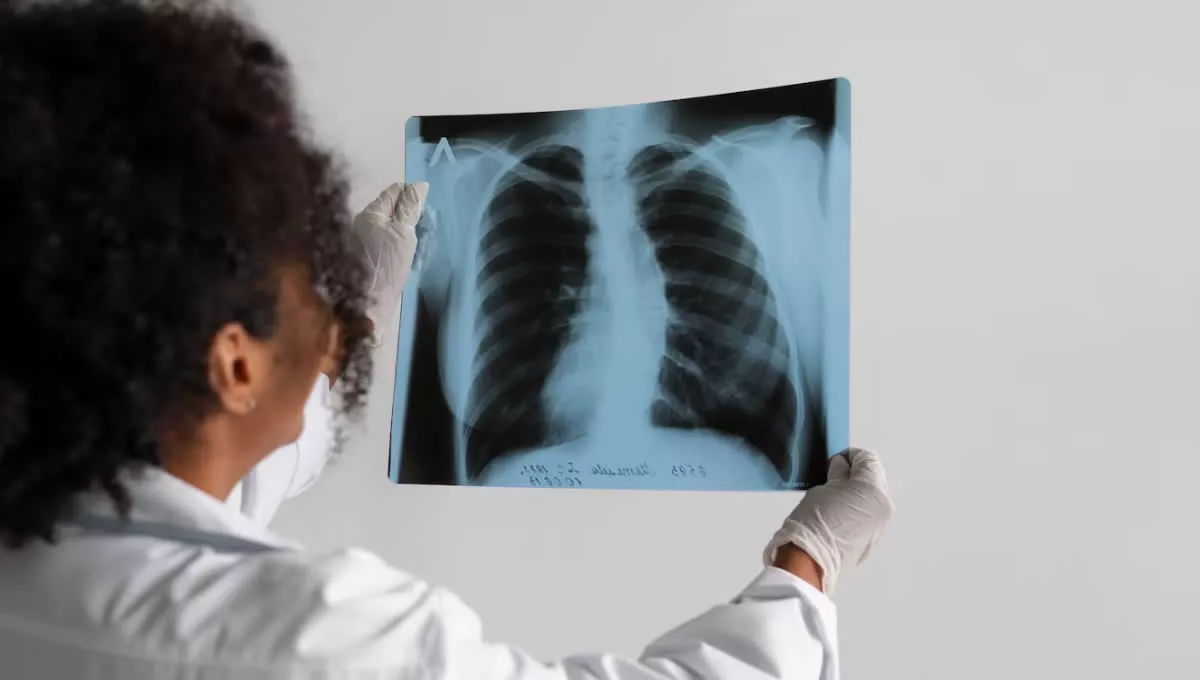

No tiene cura, acaba con el correcto funcionamiento del pulmón y, poco a poco, destruye zonas del hígado, páncreas e incluso el sistema reproductor. Estas son algunas de las características de la fibrosis quística, una patología que afecta a más de 25000 personas en España y que, gracias al cribado neonatal, puede ser tratada a tiempo. También gracias a los donantes, que hacen posible el trasplante a quienes más lo necesitan.

Sin embargo, no fue hasta tiempo después cuando el trasplante de Iria se hizo posible. En un primer momento, en septiembre de 2001, la paciente recibió una llamada del hospital para informarle de que habían encontrado donante. No obstante, tras pasar por todo el proceso, y “estando en el quirófano, vieron que el órgano no era compatible”, continúa explicando la paciente.

Pero meses después, en mayo de 2002, Iria recibió un trasplante de pulmón compatible. “Me llamaron un sábado por la mañana, me dijeron que venía una ambulancia a recogerme y, después de pasar por todo el proceso, esta vez sí que funcionó”, cuenta Saavedra. “Los últimos meses antes del trasplante mi vida fue en el hospital”, recuerda.